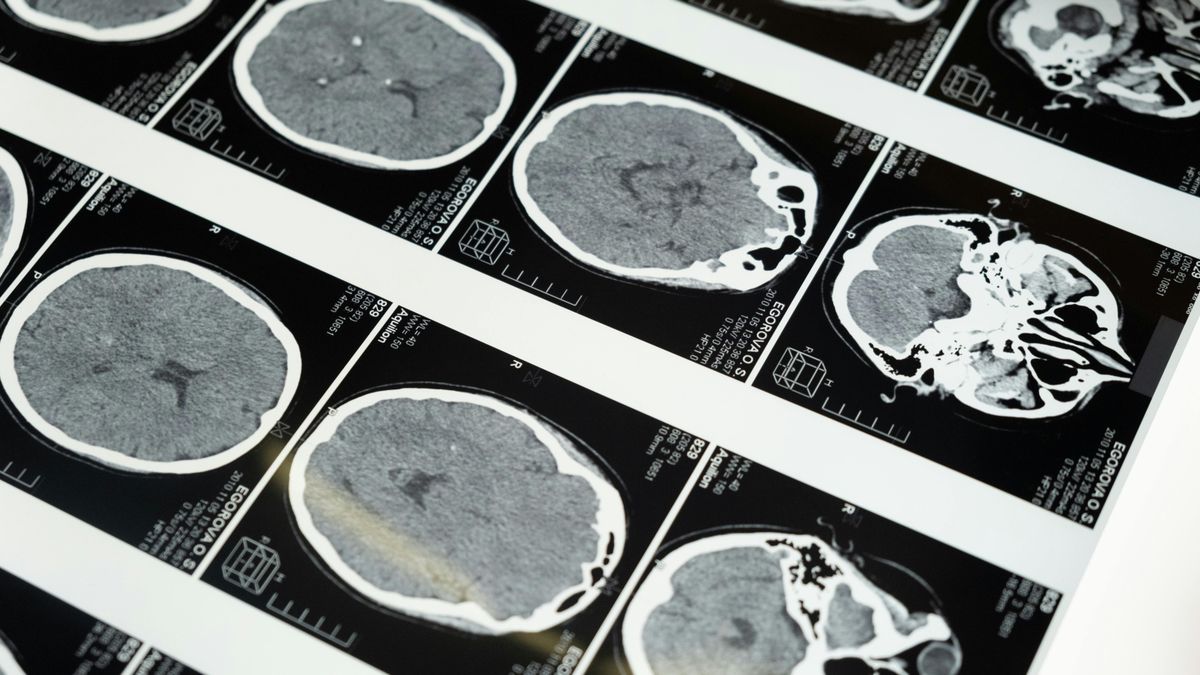

Katie-Jo Bartlett furcsa tüneteket kezdett érezni. Azt mondták neki, csak a vizsgák miatt stresszel. Később agydaganatot diagnosztizáltak nála.

Szülei azt gondolták, csak a vizsgák miatt stresszel. Később kiderült, hogy agydaganata van. A lány panaszait akkor kezdték komolyan venni, amikor egy nap összeesett a mosdóban – közölte a Mirror.

Katie-Jo Bartlett tüneteit sokáig elbagatellizálták, egészen addig, amíg elvesztette az eszméletét egy mosdóban, és kórházba szállították.

A 19 éves, newcastle-i fiatal tüneteinek megjelenésekor látászavarai voltak.

Később az egészségügyi dolgozók megállapították, hogy Katie-Jo súlyos vízfejűségben szenved – ez az agyban felgyülemlő folyadék rendellenes felszaporodását jelenti. Azonnal átszállították a Newcastle-i kórházba, ahol folyadékelvezető beavatkozásokat végeztek rajta.

A későbbi MRI- és CT-vizsgálatok kimutatták, hogy agydaganata van.

Ezt követően Katie-Jón több műtétet hajtottak végre, amelyek során egy söntöt ültettek be, hogy csökkentsék a koponyán belüli nyomást. Sajnos a daganat nem operálható, azonban nyolc havonta MRI-vizsgálattal ellenőrzik, hogy nem növekszik-e az elváltozás. A sönt mellékhatásaként gyakran fáradtságot tapasztal.